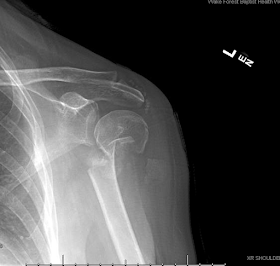

The following case illustrates the challenges and difficulties in treating a patient who is young and active and unfortunately has a failed prior reconstruction for anterior traumatic instability associated with a seizure. Initially, he was diagnosed with an anterior dislocation, fracture of the greater tuberosity, and soft tissue Bankart lesion. The first operation performed elsewhere was an open Bankart repair with repair of the rotator cuff and resection of the CA ligament. When referred to us he had a chronic locked anterior shoulder dislocation, a large size Hill Sachs lesion and chronic rotator cuff deficiency. Although, arthrodesis or reverse total shoulder replacement are the alternatives, due to his young age, an attempt was made to reduce the dislocated humerus and prevent further dislocations. The was clinically anterior superior escape, during surgery it was found that the subscapularis was ruptured, and the CA ligament was resected during the previous operation. The rotator cuff repair that was performed primarily had failed. An Eden Hybbinette procedure was chosen because the alternative Latarjet would have provided an insufficient -small bone - restraint to anterior directed forces and tendency for anterior dislocation.

Postoperative images after the Eden Hybbinette are shown below: